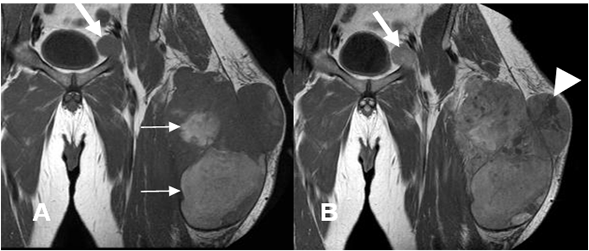

Fig 110 C. Sarcoma pleomórfico indiferenciado.

A: RM coronal en T1 simple y B: RM coronal en T1 con contraste. Igual paciente anterior. Lesión tumoral con zonas hiperintensas en la fase simple, por sangrado subagudo. (Flechas delgadas). Un gran porcentaje del tumor realza con el contraste, pero se identifican zonas hipointensas, por necrosis. (Punta de flecha). La adenopatía inguinal izquierda, también realza con el contraste. (Flecha gruesa).